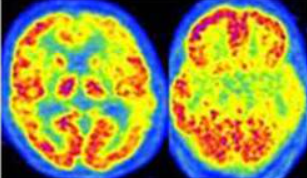

Alzheimer tipico (amnesico)

Nella forma classica, l’ipometabolismo inizia solitamente nelle regioni della Default Mode Network (DMN). Le aree precocemente colpite includono la corteccia cingolata posteriore e il precuneo.14 Successivamente, il deficit si estende alle cortecce associative temporo-parietali (giro angolare, giro temporale medio e inferiore) e, nelle fasi più avanzate, ai lobi frontali (cortecce prefrontali associative).

Un segno distintivo dell’AD è il risparmio relativo della corteccia motoria e sensoriale primaria, della corteccia visiva primaria, dei gangli della base, del talamo e del cervelletto.